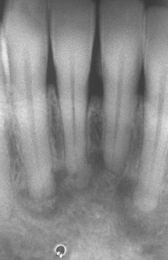

periapical cemento-osseous dysplasia